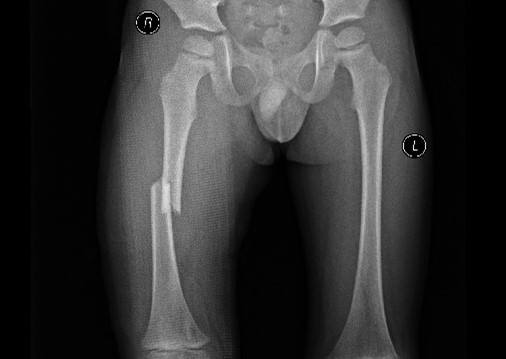

术前影像显示,皓皓的右侧股骨中段骨折错位。

小儿骨科病房。经检查,皓皓被确诊为“右股骨中段骨折并错位”。